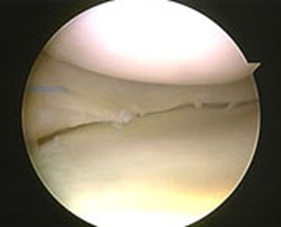

Procedura de implantare a meniscului artificial ACTIFIT

Dispozitivul este destinat defectelor parțiale de menisc. Cornurile anterioare și posterioare ar trebui să fie intacte, iar marginea meniscală ar trebui să fie stabilă.Pacientul trebuie să aibă o margine meniscală intactă, cu cornurile anteriorare și posterioare prezente, pentru a permite atașarea Actifit. Procedura se realizează artroscopic, de obicei cu anestezie generală sau cu rahianestezie. Dacă leziunea meniscală inițială nu poate fi suturată (reparată), țesutul afectat este îndepărtat aproape la fel ca în cazul unei meniscectomii parțiale până se ajunge la o zonă cu un bun flux sanguin.

- Defectul meniscal este evaluat.

- Dacă defectul nu poate fi reparat, zona este aranjată și pregătită pentru Actifit.

- Se măsoară Actifit pentru a asigura o potrivire perfectă a zonei afectate și se taie pe masa chirurgicală cu ajutorul unui bisturiu.

4. Implantul este apoi plasat artroscopic în zona aranjată și pregătită a genunchiului afectat.

5. Se pot utiliza mai multe tehnici de sutură pentru securizarea Actifit în marginea meniscală rămasă și cornurile posterioare/anterioare, cum ar fi all-inside, inside-out sau outside-in, în funcția de dorința chirurgului, precum și în funcție de localizarea defectului.